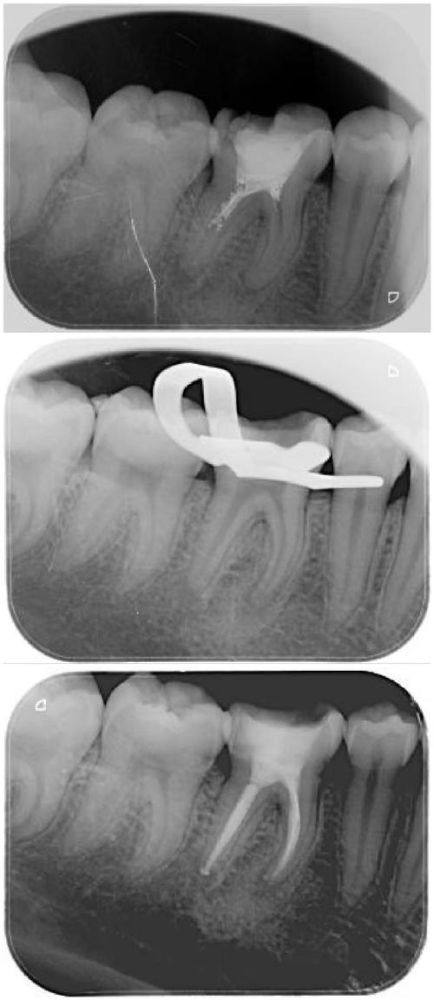

根管治疗:能够精细处理牙髓病变问题,保留患牙,有效缓解牙痛症状,操作细致严谨,尽可能减少治疗过程中的不适感。